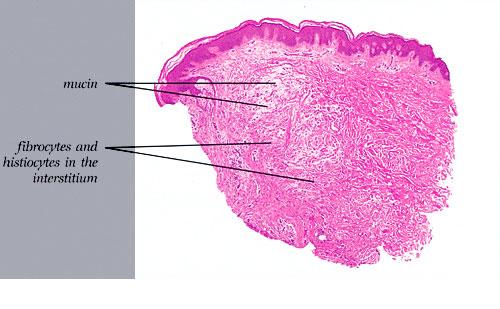

The mucin found in these six diseases represents an increase in the mucin that is normally present in the ground substance of the dermis. It consists of proteins bound to hyaluronic acid (hyaluronan), which is an acid mucopolysaccharide or glycosaminoglycan. As a result of the great water-binding capacity of hyaluronic acid, dermal mucin contains a considerable amount of water. This water is largely removed during the process of dehydration of the specimen; consequently, in routine sections, the mucin, because of its marked shrinkage, appears largely as threads and granules.

The mucin present in the six types of mucinosis stains a light blue in sections stained with H&E. It also stains with colloidal iron. It is Alcian blue-positive at pH 2.5 but negative at pH 0.5 and shows metachromasia with toluidine blue at pH 7.0 and 4.0 but no metachromasia below pH 2.0 . It is PAS negative (indicating the absence of neutral mucopolysaccharides) and aldehyde fuchsin negative (indicating the absence of sulfated acid mucopolysaccharides). The mucin is completely removed on incubation of histologic sections with testicular hyaluronidase for 1 hour at 37"C .